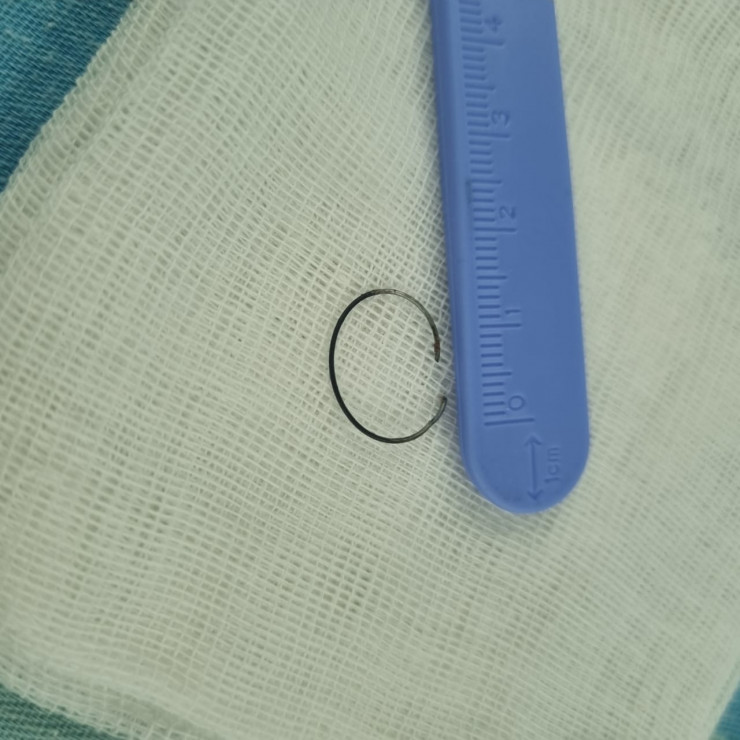

"Например, из кишечника 4-летнего малыша вытащили кольцо от связки ключей. Родители три недели не догадывались, что их ребенок проглотил его. Хотя он жаловался на боли в животе, рвоту. Потом обратились к нам. Под общим наркозом на ФГДС мы обнаружили инородное тело в 12-перстной кишке и извлекли его. Был еще случай недавно: мы вытащили из дыхательных путей 14-летнего подростка фонарик от зажигалки. Примечательно то, что юноша месяц ходил и никому не рассказывал об этом, пока при обследовании на рентгене случайно не обнаружили инородное тело в дыхательных путях", - рассказал Серик Нусипкожаев.